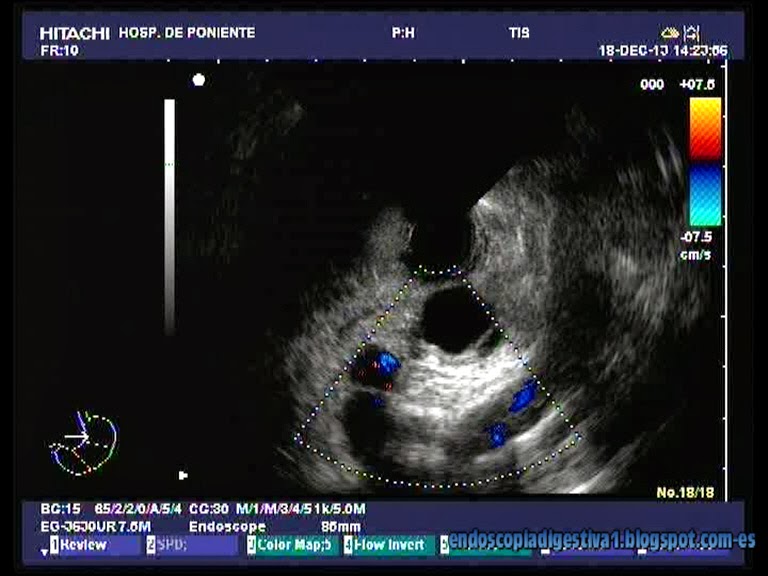

Paciente mujer de 41 años sin antecedentes de interés que en 2010 tuvo un cuadro de epigastralgia moderada autolimitada con ligera hiperamilasemia (< 500 UI/ml) sin otros hallazgos de interés. La eco abdominal practicada no reveló ninguna patología, pero en el TAC se apreció una lesión de 16 mm ubicada en el cuerpo del páncreas, regular, quística y con paredes bien definidas junto a refuerzo posterior. Se realizó una USE sectorial con punción donde se obtuvo un líquid claro con citología inflamatoria y concentraciones bajas de CEA y amilasa. Se estableció el diagnóstico de quiste simple pancreático. El protocolo de actuación posterior ha sido la realización de una USE radial anual, donde la lesión no ha presentado cambios respecto de los primeros estudios.

Los quiste simples pancreáticos son de origen congénito y representan el 5-10 % de todas las lesiones quísticas del páncreas (son la 3ª causa mas común de lesiones quísticas en esta ubicación tras los pseudoquistes-80-90 %- y los quistes serosos). Se descubren de forma incidental al realizar una ECO/TAC por otros motivos. Pueden presentarse de forma aislada o asociados a la poliquistosis hepatorrenal del adulto y el síndrome de Von Hippel-Lindau. La importancia clínica de estas lesiones no es muy bien conocida ya que no existen estudios de seguimiento a largo plazo. No obstante, en un estudio sobre 86 lesiones de este tipo resecadas quirúrgicamente no se encontró degeneración maligna en ningún caso. Por USE las lesiones tienen todas las características de los quistes simples de otras localizaciones (pequeños, con pared delgada, uniformemente anecoicos y sin nodularidad o elementos papilares en su interior. El tejido pancreático adyacente es normal (sin signos de pancreatitis crónica) y no hay dilatación del Wirsung. El líquido aspirado contiene pequeñas cantidades de de células inflamatorias y niveles bajos de amilasa y CEA.